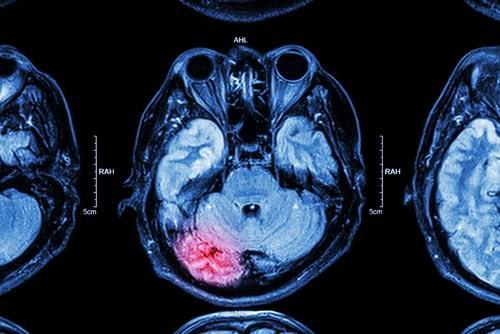

March is National Brain Injury Awareness Month. In recent years, there has been a lot of research conducted on traumatic brain injuries (TBIs), most notably concussions that are caused by sports. However, significant head trauma is often a result of a motor vehicle accident. The force of impact in a car crash can be severe, causing a driver and passengers to slam their head against the steering wheel, windows, or doors. In many head injuries, the brain is negatively affected, and the long-term consequences of it can be serious, often requiring medical treatment such as surgeries or therapy. Depending on the details surrounding the collision, a victim may be able to bring a personal injury claim against a negligent party.

Brain injuries can affect an individual’s speech, critical thinking skills, memory, and more. Physicians usually classify traumatic brain injuries into two main categories. Closed injuries do not fracture the skull but open injuries can break or penetrate the skull bone, leaving a person’s brain exposed to outside elements. This can lead to other complications, such as infections.

There are several different types of brain injuries that can occur, including:

- Hematoma - A collection of blood vessels.

- Contusion - Bruising of the brain.

- Hemorrhage - Bleeding on or within the brain’s tissue.

- Concussion - The brain is jostled around and hits the skull.

- Edema - Excess accumulation of fluid in the brain.

- Skull fracture - A crack or break in the skull.